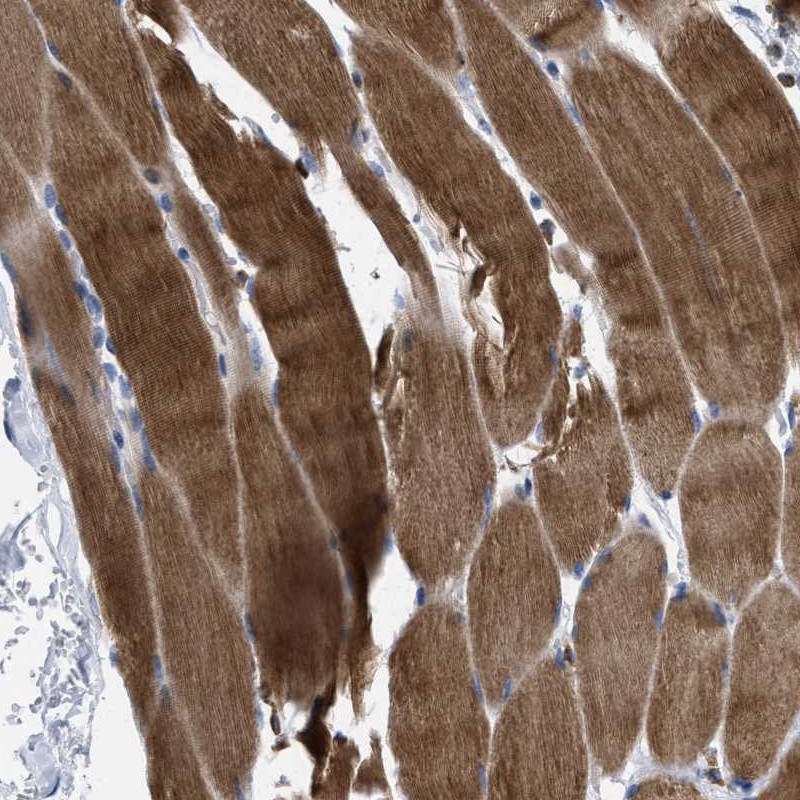

Immunohistochemical staining of human skeletal muscle shows strong cytoplasmic positivity in myocytes.